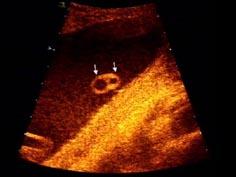

问题 如图,为一孕妇34周时,羊水内漂浮所见管道结构(横切),最可能的诊断是 ( )

选项 A、单脐动脉 B、正常图象 C、脑膜膨出 D、淋巴管囊肿 E、脊柱裂

答案 A